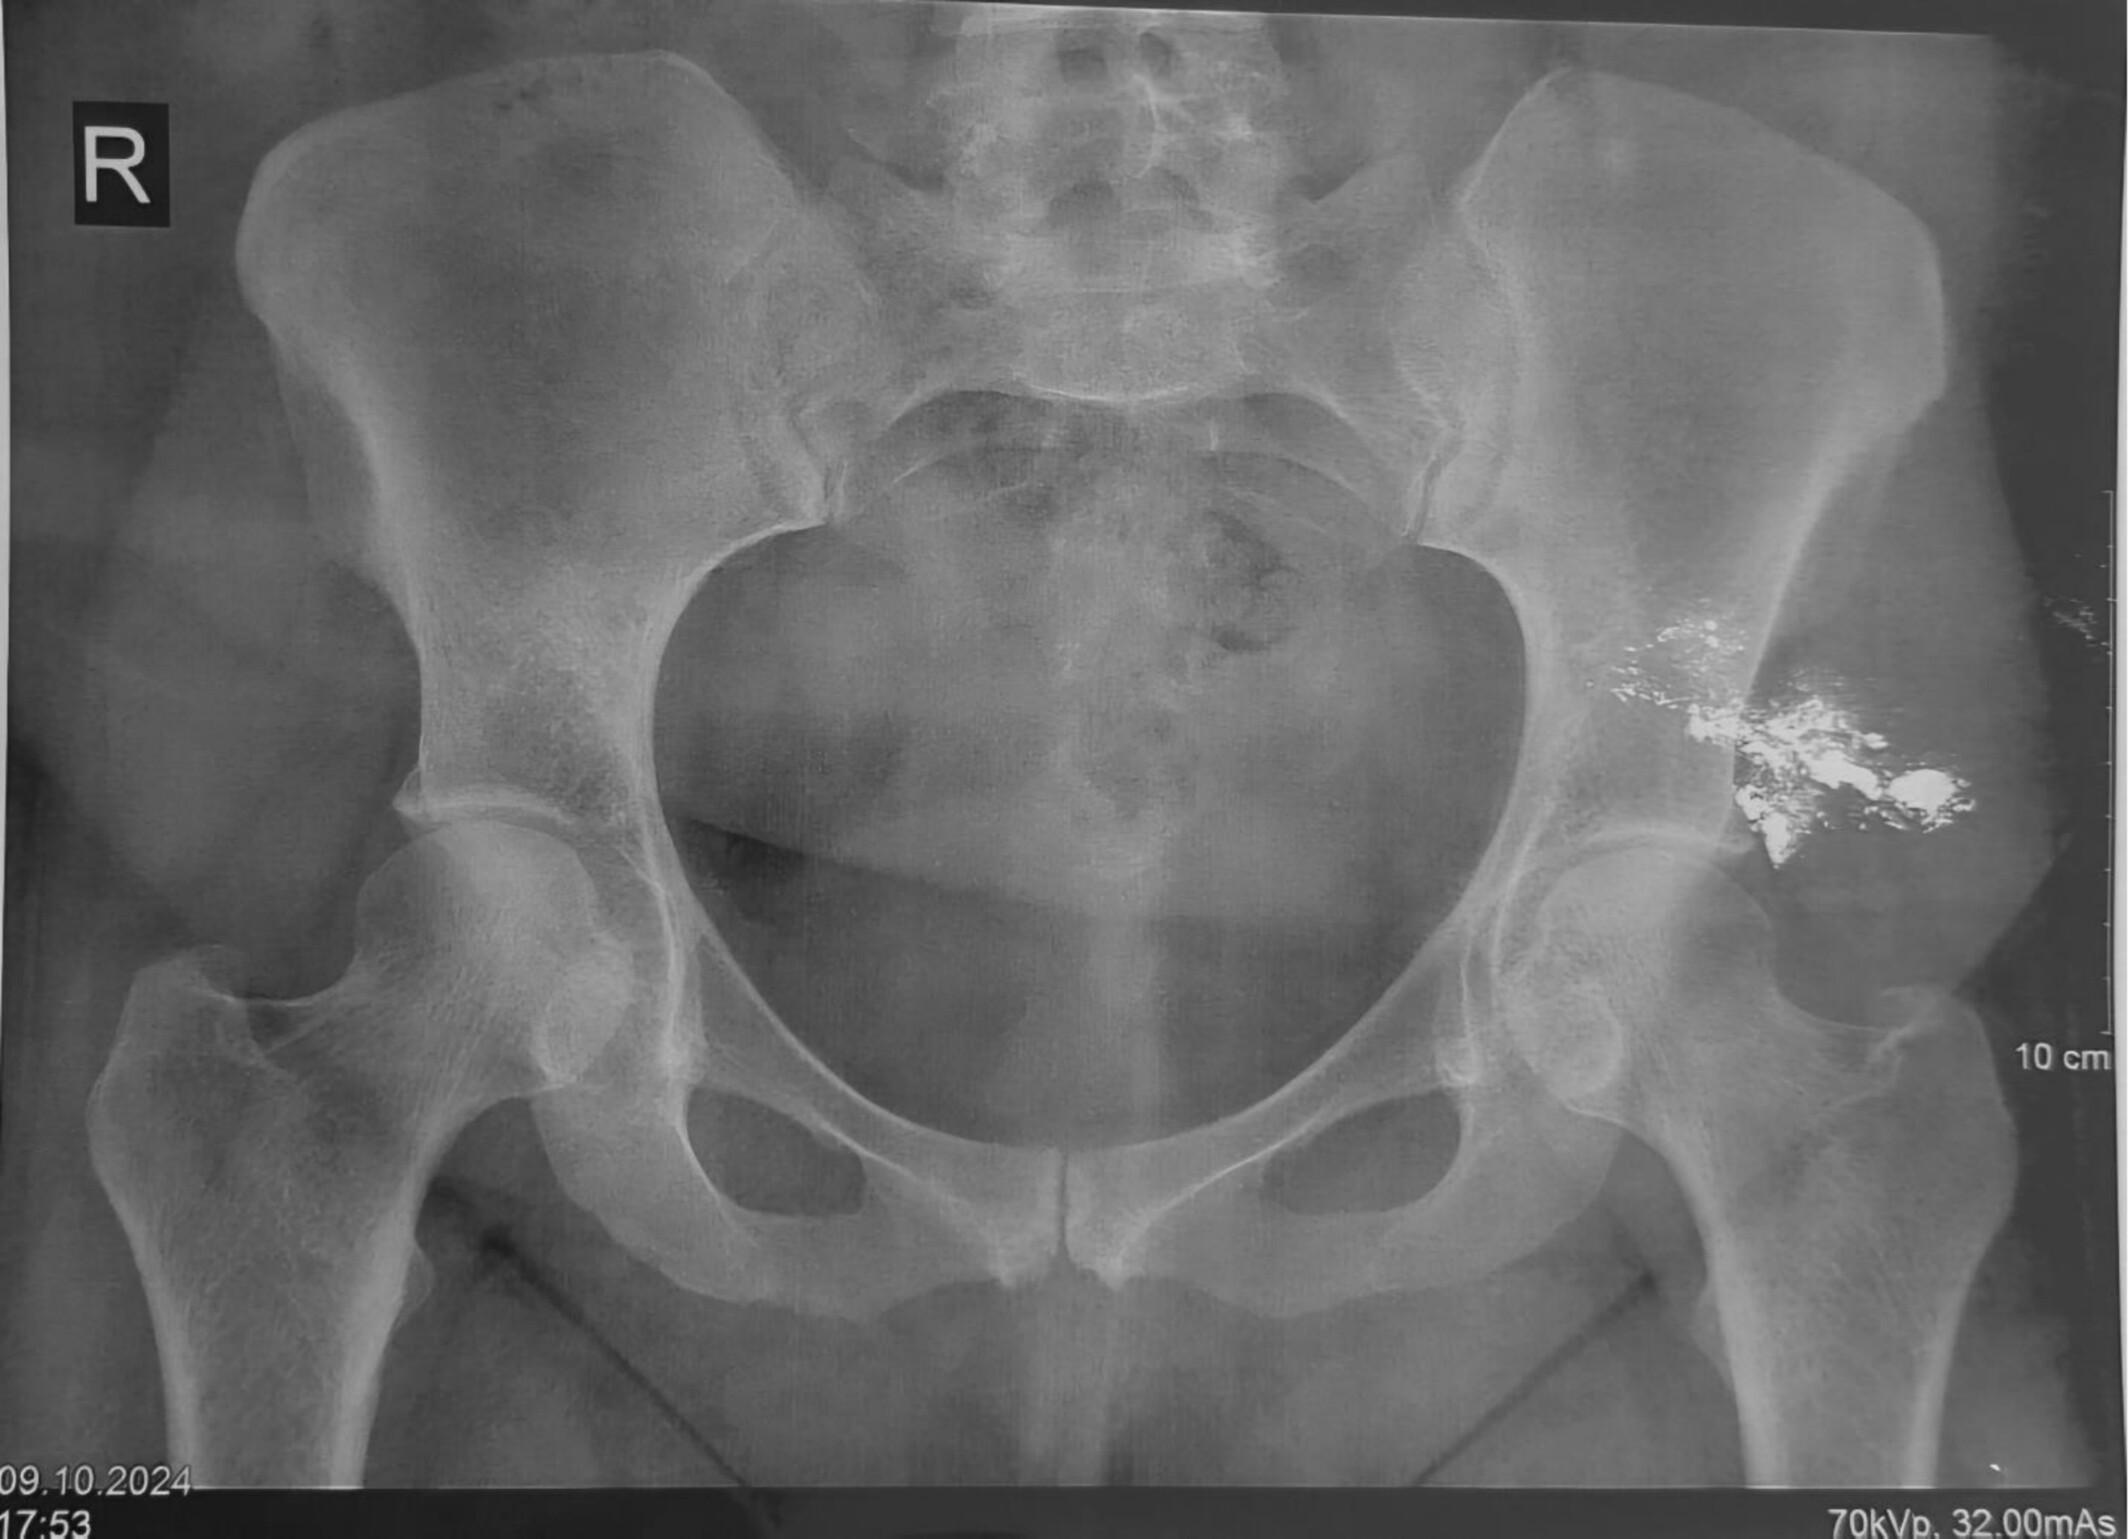

Женщину обследовали в токсикологическом отделении университетской больницы в Тегеране. На рентгене врачи четко увидели локальное скопление плотного контрастного вещества. Анализы подтвердили, что серебристая жидкость из ранки — это ртуть. При этом у женщины не было классических симптомов отравления. Но в крови и моче обнаружились высокие уровни ртути.